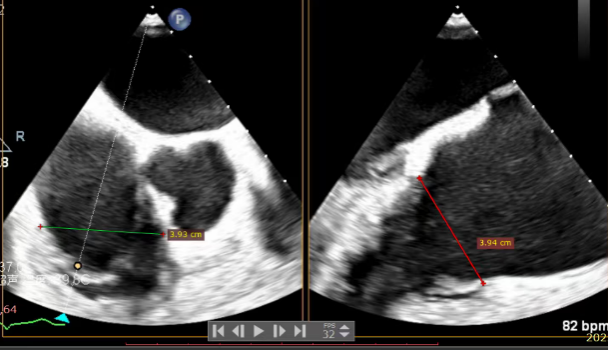

Echocardiographic Assessment: Echocardiography revealed left atrial enlargement. The left atrial appendage (LAA) orifice was 32mm with no thrombus inside. Tricuspid regurgitation was extreme (average vena contracta 18mm). Regurgitant jets were located at the anterior-septal, central, and posterior-septal commissures, with a central gap measuring approximately 13x5.9mm. The annulus was mildly dilated (average diameter 43mm). The tricuspid leaflets showed thickening and degenerative changes.

Systolic Tricuspid Annulus: Circumference 138mm, Area 1468mm².

Diastolic Tricuspid Annulus: Circumference 145mm, Area 1646mm².

Annular area reduction: 50%

- Annulus Area Reduction: Decreased by 50%.